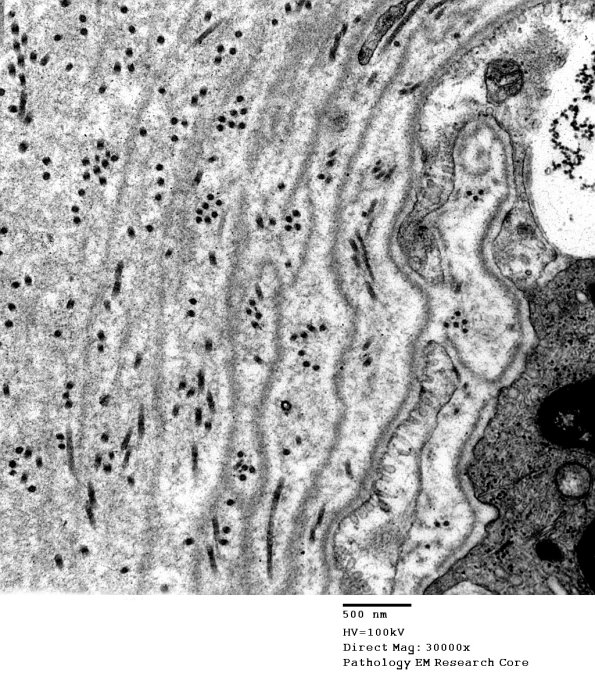

The endoneurial vasculature is markedly thickened by alternating circumferential basement membranes and collagen, a pattern most commonly associated with diabetic neuropathy. (electron micrographs)